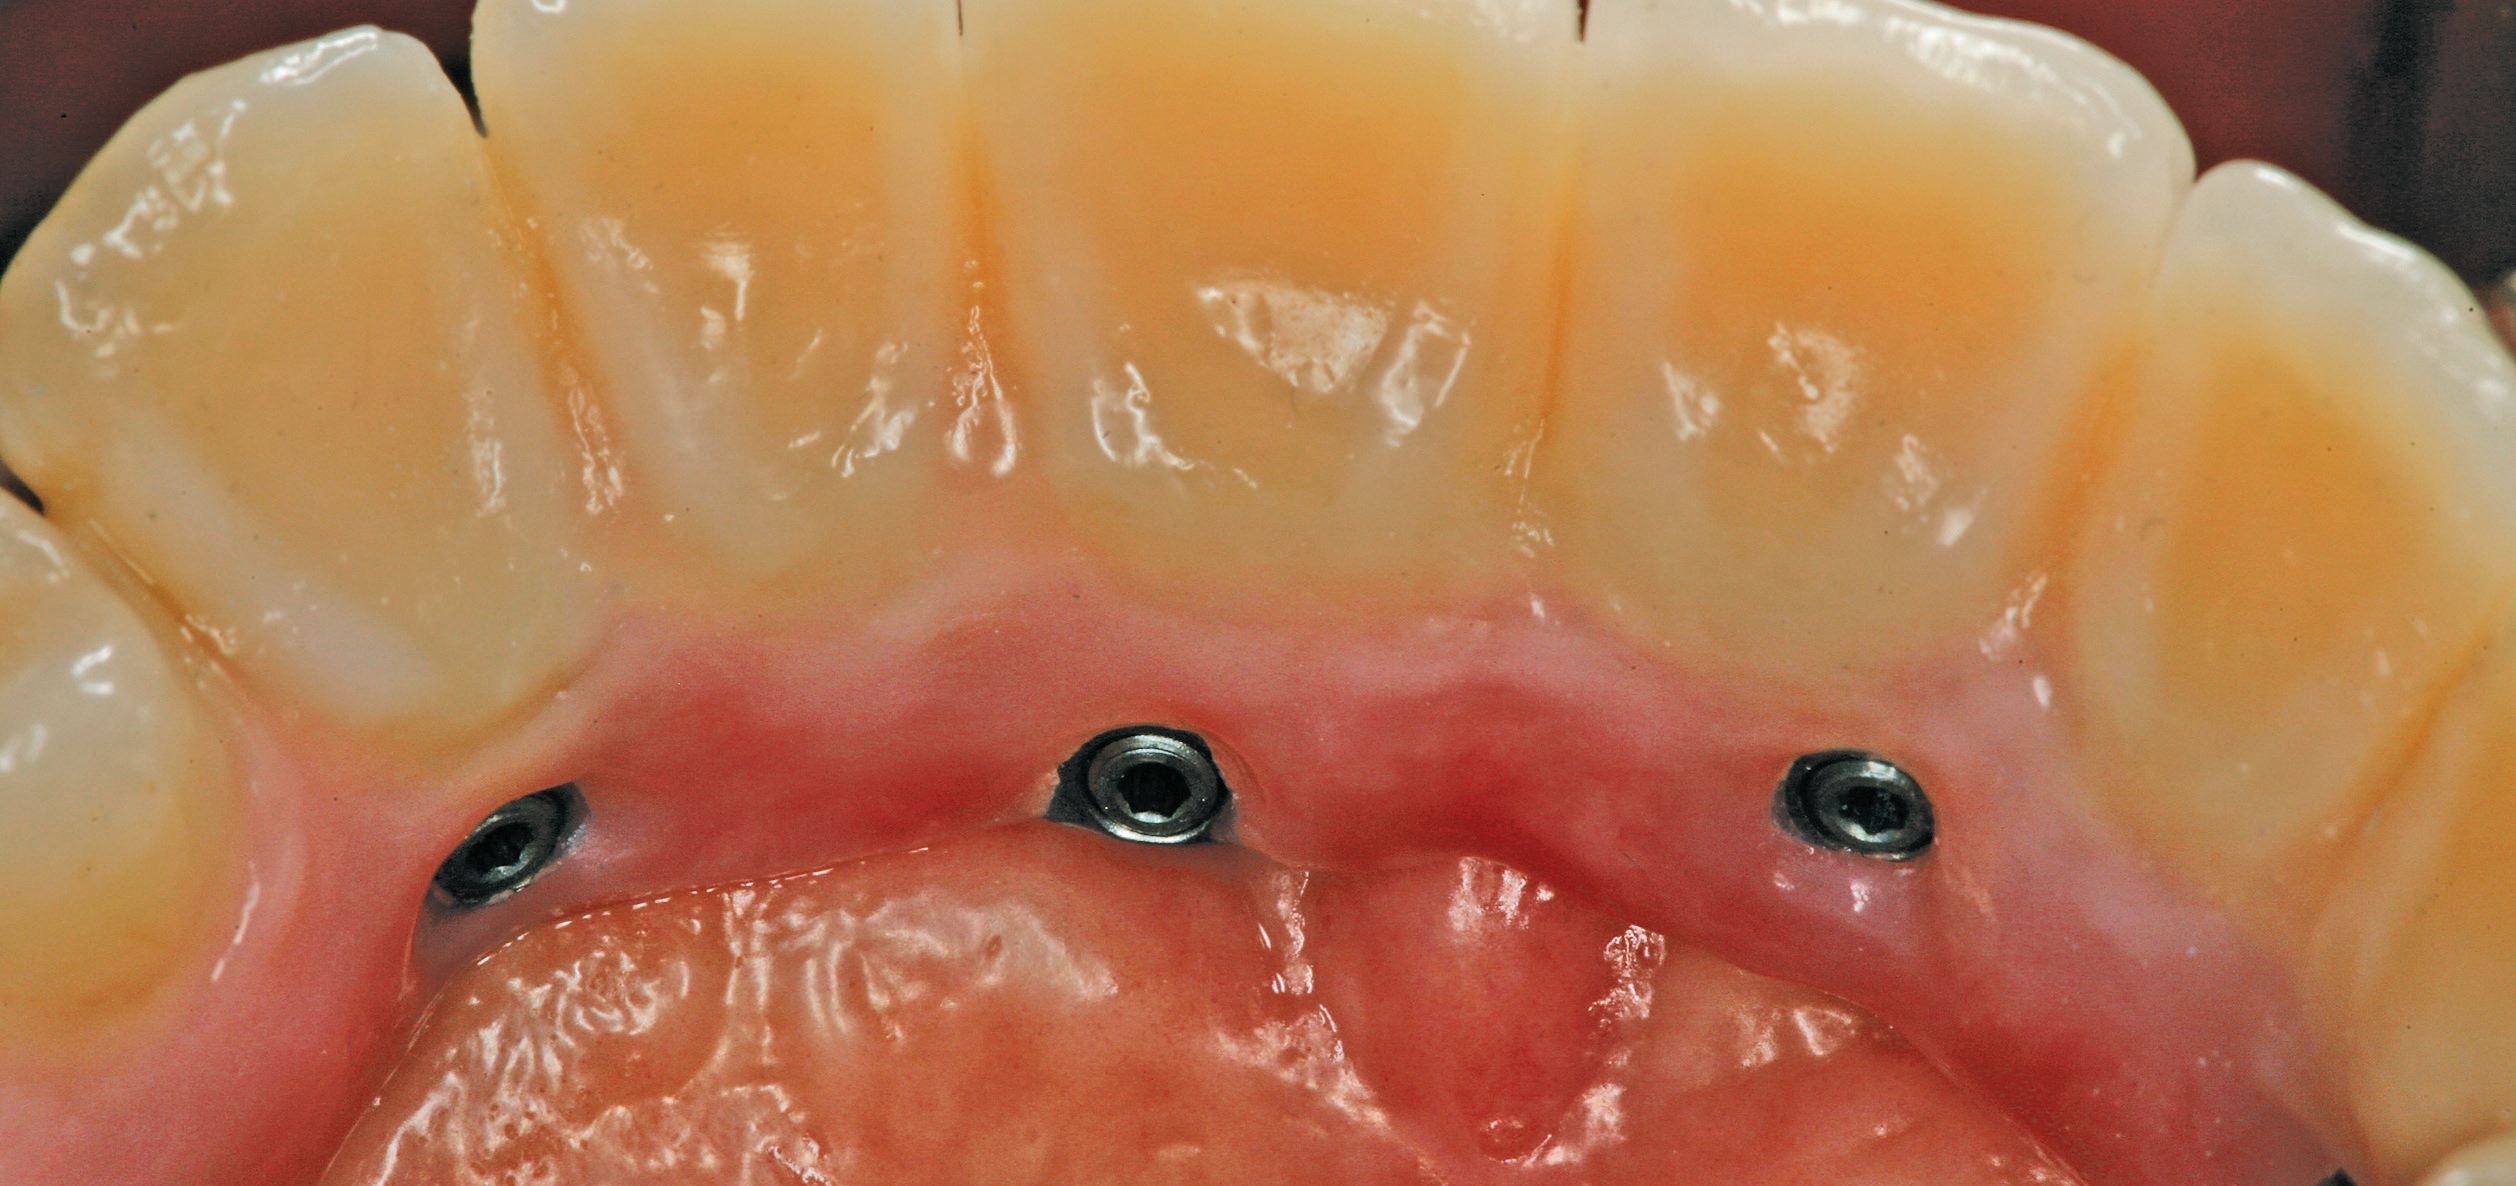

Eingliederung

Das Aufschrauben der definitiven Brücke gestaltete sich problemlos. Nach Abnahme der temporären Versorgung ist die fertiggestellte Brücke über die Prothetikkappen bzw. die Verbolzungen auf den Implantaten befestigt worden (Abb. 5 und 6). Bei den posterioren Implantaten wurde der Schraubenzugang vom Zahntechniker nach vestibulär – außerhalb des sichtbaren Bereichs – gelegt (Abb. 7 und 8). Die anderen Implantate wurden im palatinalen Bereich verschraubt (Abb. 9). Aufgrund der Drei-Punkt-Fixierung ist ein Verkippen oder das Rotieren des Zahnersatzes ausgeschlossen. Da die Schraube in der Sekundärkonstruktion „gefangen“ ist, wird die Anwendung im Mund erleichtert. Ein lästiges Einfädeln entfällt. Bereits mit zwei bis drei Umdrehungen ist eine Schraube fixiert. Weder ästhetisch noch funktionell treten Beeinträchtigungen auf.